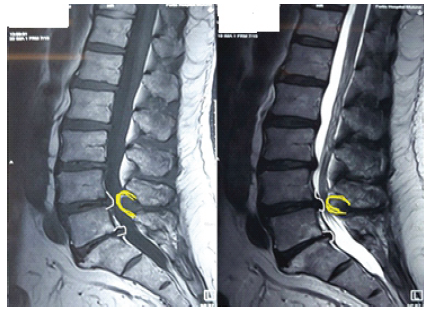

Baastrup’s Disease, a Rare Cause of Cauda Equina Syndrome: Case Report

Aniruddha Vaidya , Sushil Mankar , Nitin Pothare , Vismay Harkare

………………………………p.63-67